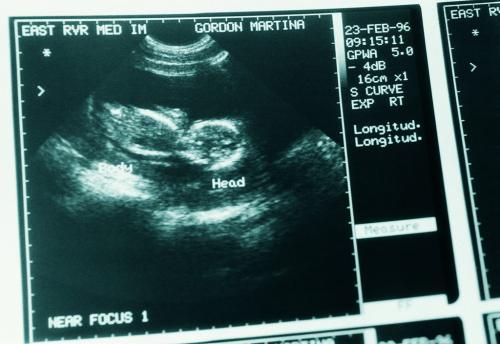

小于已经怀孕8个月了,怀孕3个月时,在我们医院建档产检。在一次B超检查时,医生发现,胎儿的左手臂有异常。

B超检查室里,医生对小于说:“根据B超来看,现在胎儿左臂有一明显囊性包块,大小约68mm×42mm。”